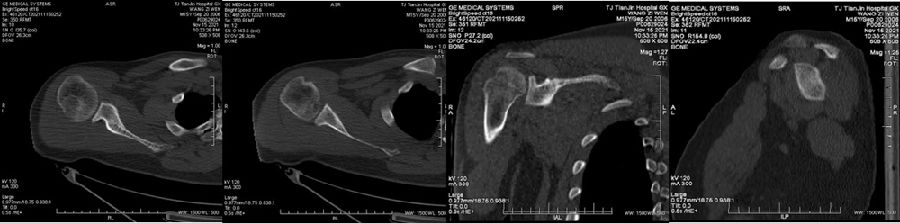

Case1:影像学评估病例,19岁,打篮球摔伤脱位。

图23 首次脱位

图24 打球再次受伤,复发脱位

图 25-27 MRI

双侧CT三维扫描显示:健侧肩胛盂宽度D=25.9,患侧D=23.9,患侧肩胛盂骨性缺损d=6.2,骨性盂唇缺损面积d/D为23.9%(<25%)。肩胛盂轨迹GT(83%D-d)为15.3mm。

图28双侧CT三维扫描

图29 Hill-Sachs间隙为13.8mm(<15.3mm)

图30 评估结果

评估报告提示:右肩胛骨关节盂前下缘撕脱骨折,符合骨性bankart损伤。右肱骨头后上缘凹陷骨折,符合Hill-Sachs损伤。Hill-Sachs间隙为13.8mm(<15.3mm),为轨迹内肩关节前脱位。